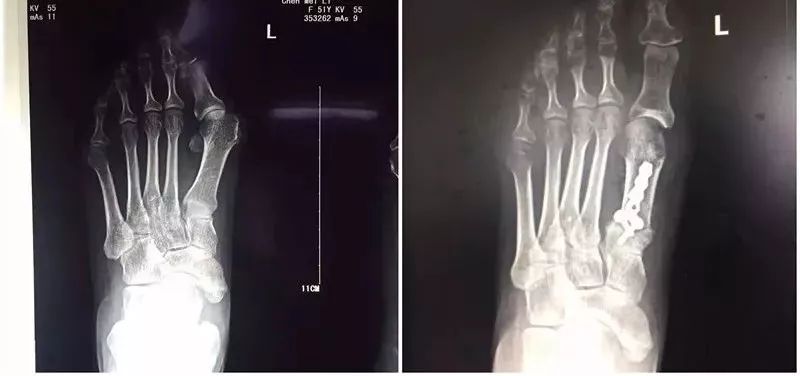

足骨骨折

石膏固定

月余今拆有记

余献增(浙江金华)

今朝折柳石膏别,梅落芽青冷暖知。未命名_副本13.jpg